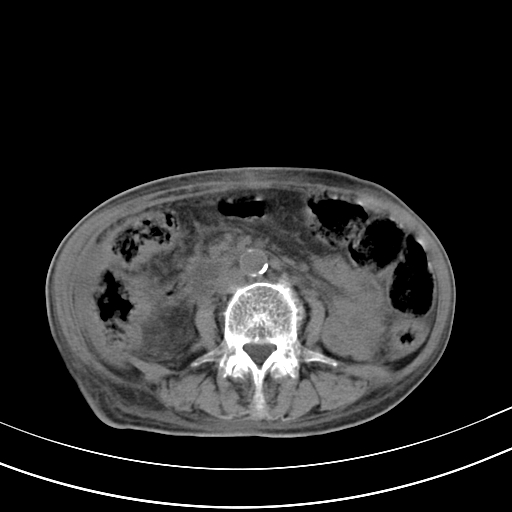

病人上腹部胀痛拌全身黄染八天

右侧少量胸水,胆囊增大,肝内胆管扩张,肝门部结构杂乱,建议增强。

肝内胆管及胰管扩张考虑为胰头区占位,肝门淋巴结增多,肝内多发低密度影,考虑为转移。门脉高压,脾大,胆囊大。

肝内胆管及胰管扩张,胰头增大考虑为胰头区占位,肝门淋巴结增多,考虑为转移。建议增强,脾大,胆囊大,壁厚,慢性胆囊炎。胃壁好像也增厚,且有一肿物。

1)考虑胰头癌并胆系低位梗阻;建议行ct增强扫描检查。2)慢性胆囊炎。3)脾大。4)少量腹水。5)双侧少量胸腔积液。